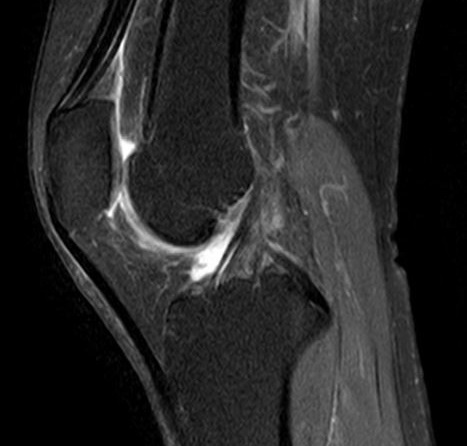

MRI画像

正常

膝蓋腱炎

膝蓋腱周囲(黄色矢印)に信号変化があり、炎症が見られます。

膝蓋腱実質(赤矢印)まで信号変化があり、膝蓋腱の損傷が疑われます。